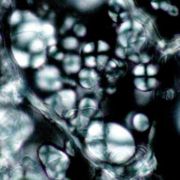

韓国産の延胡索ではでんぷん粒が認められたが、中国産の延胡索ではでんぷん粒は認められなかった。これは、韓国産は生干しであるため、デンプン粒がつぶれずに認められるのに対して、中国産では湯通し加工の過程で、でんぷんが糊化しているためだと、考えられる(糊化したでんぷんは、偏光下でも光らない)。

| ○糊化でんぷん <中国産> |

○でんぷん粒 <韓国産> |